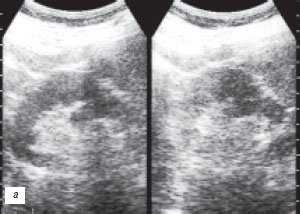

Наиболее частой причиной псевдоопухоли была "гипертрофия" столбов Бертена или "перемычки" паренхимы почек - у 153 (86,4%) пациентов (рис. 3 г-е). "Перемычки" паренхимы были отмечены не только при различных удвоениях чашечно-лоханочных систем почек, но и при различных их сращениях и незавершенных поворотах почек.

Рис. 3 (г-е). Псевдоопухоль гипертрофия Бертена (неполная "перемычка" паренхимы) в среднем отделе правой почки.

г) Эхограмма.